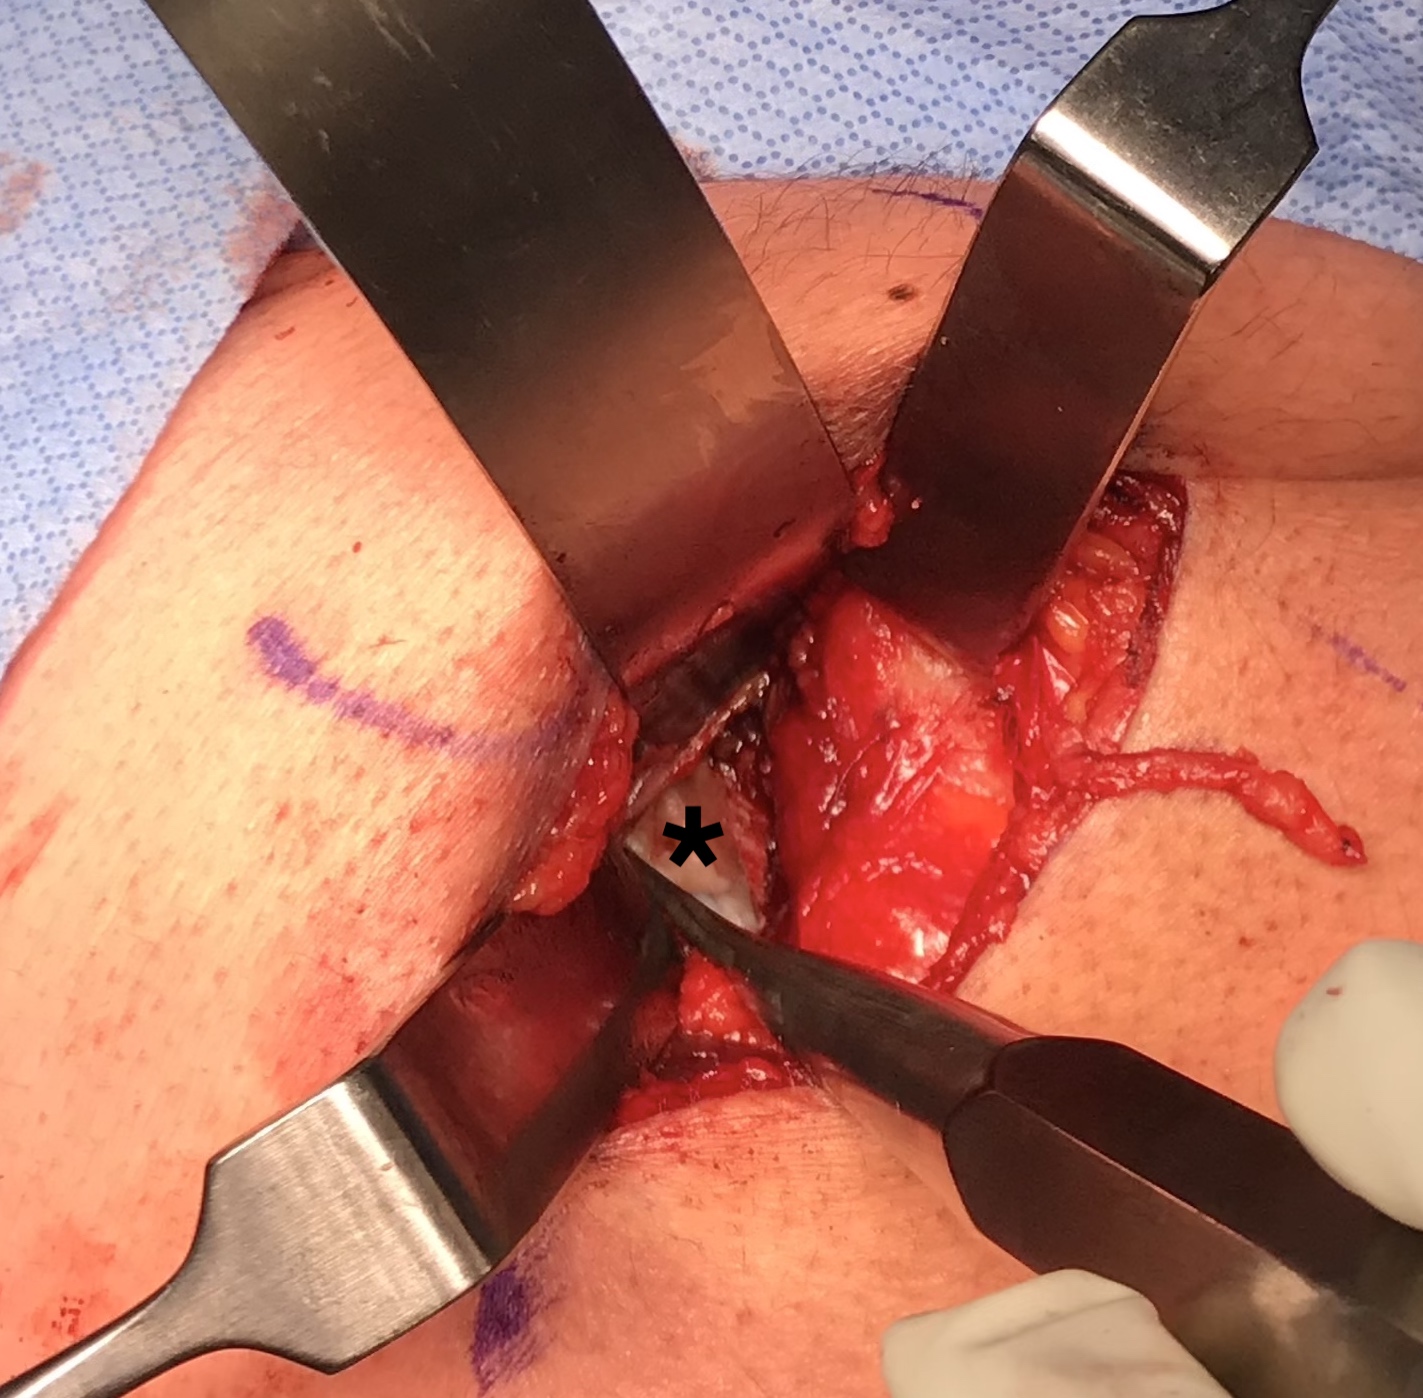

Expose ischial tuberosity

- superior retractor on ischial tuberosity

- medial and lateral retractors, care with sciatic nerve

- use osteotomes to create bleeding

- 2 - 3 suture anchors, double loaded

Exposing ischial tuberosity (*) with Cobb retractor